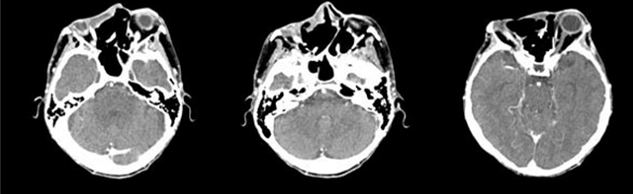

In December 2020, the patient showed a very extensive lesion (delete dome-shaped) measuring 12 × 5 cm in diameter that affected the right orbit, majority of the forehead and nose, and reaching to the left orbit. The mass presented ulceration and neovascularization. Due to pain and general malaise, the patient finally accepted to undergo head and maxillofacial computed tomography (CT) scan that showed wide destruction of the surrounding tissues, including bone structures of nose, right jaw, right orbit, anterior cranial fossa, pterygopalatine fossa, and right infratemporal fossa (Figure 1).

Sonidegib was well tolerated and led to reduction of pain, burning and itching from the first days of treatment. After only 37 days of therapy, the lesion was significantly reduced in size and flattened (Figure 3). In subsequent weeks, there was a constant progressive reduction of the tumor mass. After four months of therapy the lesion was flat (Figure 4) and, as shown on head and maxillofacial computed tomography (CT) scan (Figure 5), the process of destruction of surrounding tissues stopped almost completely.

Figure 5: Head and maxillofacial computed tomography (CT) scan after four months the start of sonidegib therapy.